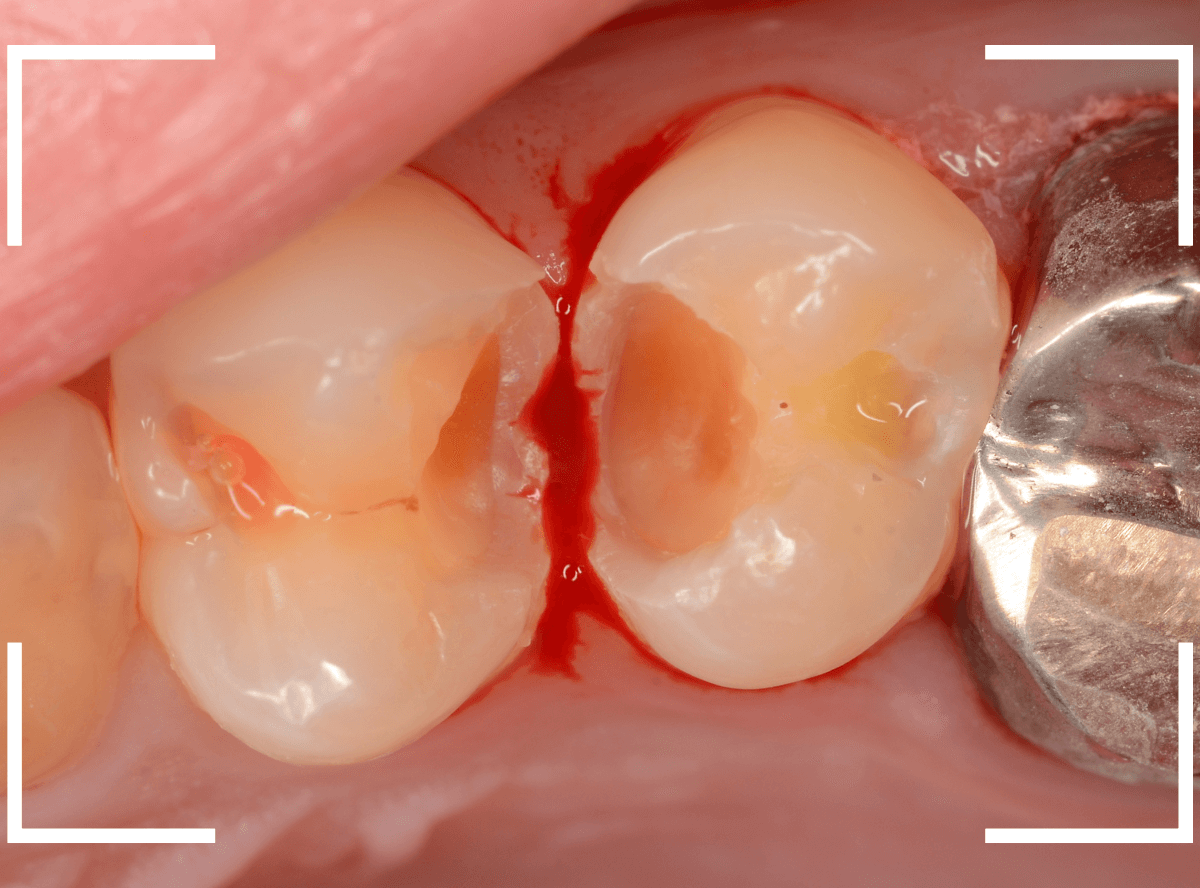

Case.19 神経まで達する大きな虫歯

「歯に違和感がある」という訴えで来院された患者さんです。

後ろの歯との間にぽっかり穴が開いているのがわかります。

このような場合、大抵は中で大きな虫歯になっています。

レントゲン写真で確認します。

青い部分が歯の神経、赤い部分が虫歯です。

レントゲン写真では、手前の歯との間も大きな虫歯になっているのがわかります。

そして、前後ともに神経まで達してしまっている虫歯に見えます。

治療を開始します。

少し削ったら、予想どおり大きな虫歯が出てきました。

虫歯が深いので、いつも以上に慎重に治療をすすめます。

赤くう蝕検知液で染まっている部分が虫歯です。

手前側は珍しく、レントゲン写真から予想される虫歯よりも小さかったです。

全ての虫歯を除去したところです。

やはり虫歯は大きく、歯の神経が一部露出する状況でした。

神経の中には血管もつまっていますので、出血するわけです。

神経を残せる可能性は半々といったところですが、神経を保護するお薬をつめた上にセメントで蓋をしました。

これでお痛みが出ないか、しばらく経過観察が必要です。